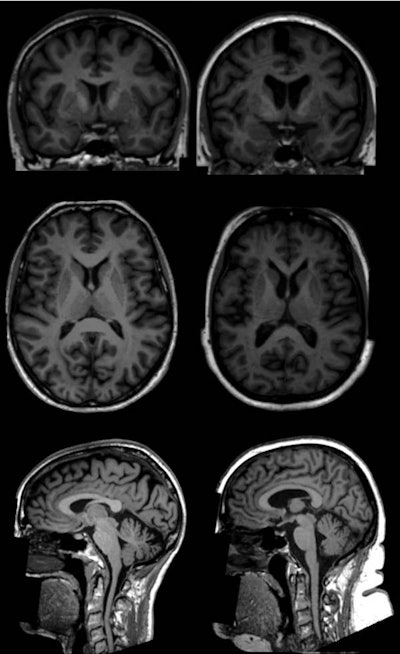

T1-weighted brain MR images show examples (coronal, top; axial, middle; and sagittal, bottom) of two women (age 65) in the U.K. Biobank study. One subject has a body fat percentage of 13% (left), while the other woman has a body fat percentage of 49% (right). MR images show lower volumes of subcortical gray-matter structures in the individual with higher total body fat percentage (right). Images courtesy of Radiology.The smaller volume of gray matter could mean a loss of neurons, while changes to the white matter could adversely affect the transmission of signals within brain networks, the researchers noted. Given that gray matter is known to play a role in the brain's food-reward circuitry, the alterations could make it more difficult for obese people to control their weight, Dekkers and colleagues posited.